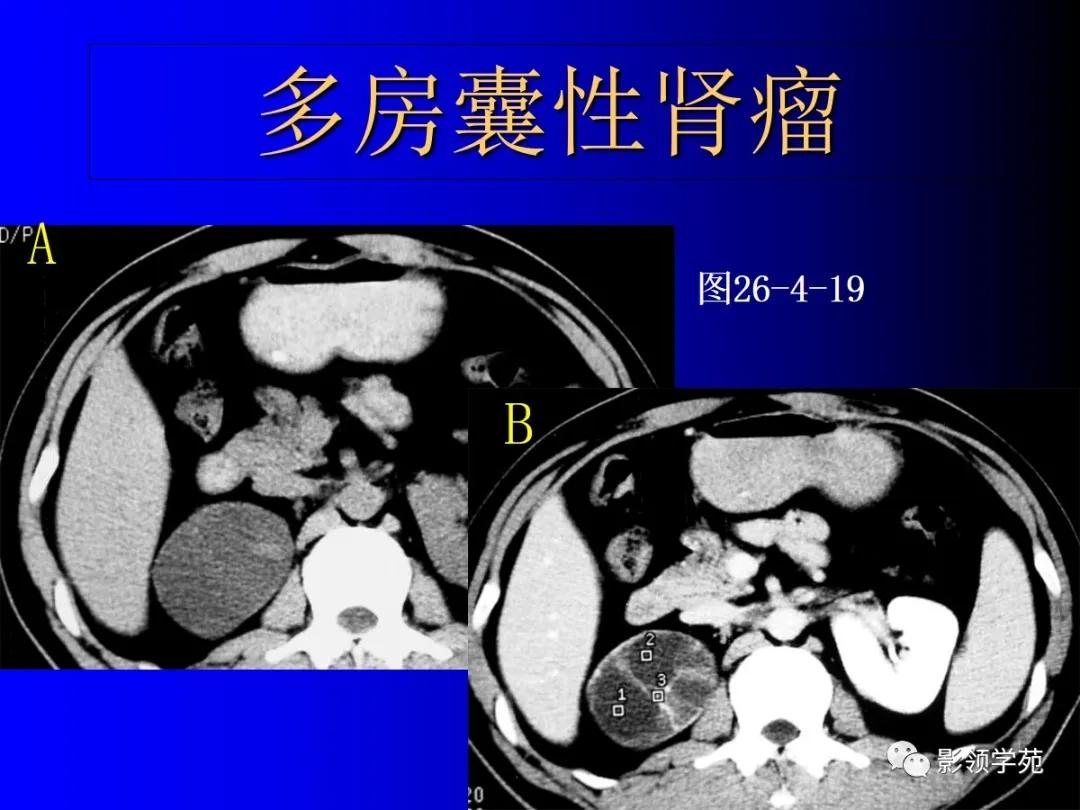

4、多房囊性肾瘤multilocular cystic nephroma

非遗传性的囊性病变。

囊壁内衬立方或扁平上皮。

多房囊腔间互不交通,伴完整的纤维分隔。

恶性者即多房囊性肾癌。

12、肾癌囊变和多房囊性肾癌

多房囊性肾癌有完整分隔